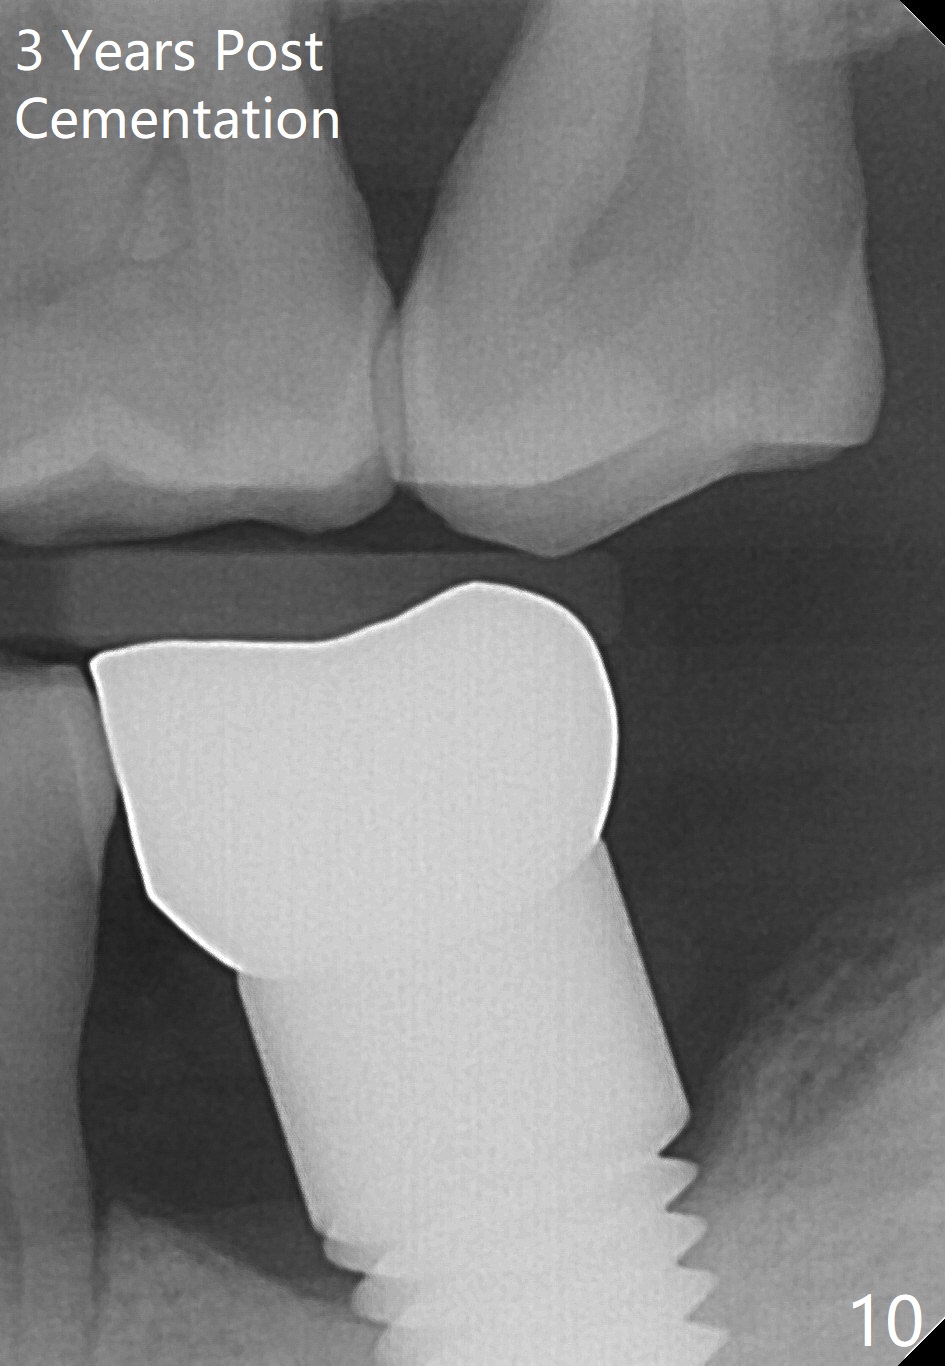

There is no bone resorption 6 months post cementation (12 months postop, Fig.8,9).  Mild bone resorption is observed 3 years post cementation (Fig.10).  It may be related to the large implant (7 mm) in association with chronic periodontitis and bruxism.   The roots of the teeth #19 and 30 fracture 6 years 5 months post cementation at #18 (Fig.11).  Since gingival recession is severe at #18 probably related to the large implant, the one at #19 will be designed small.